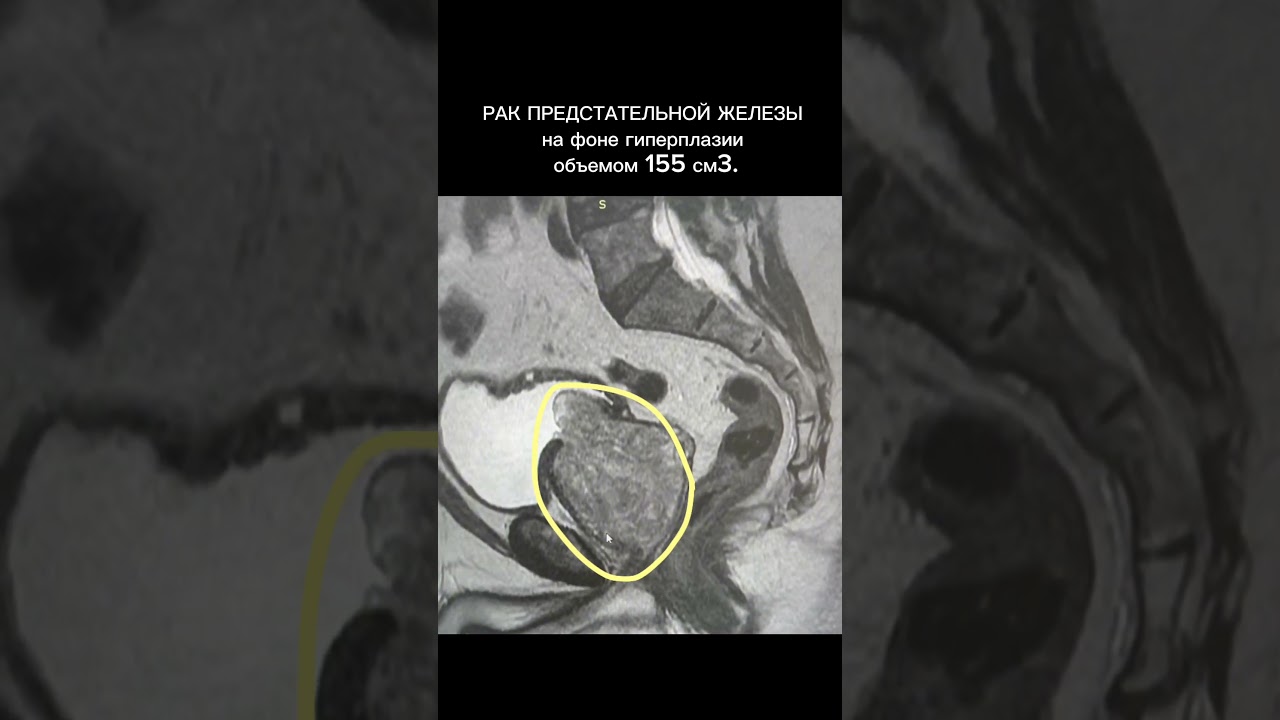

В тазу могут возникать различные опухоли, включая доброкачественные и злокачественные образования. К ним относятся миомы матки, кисты яичников, опухоли простаты, а также рак шейки матки, рак яичников и рак прямой кишки. Кроме того, могут встречаться метастатические опухоли, которые распространяются из других органов.